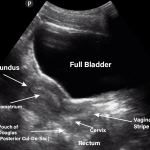

Pelvic Ultrasound: A Non-Invasive Imaging Tool for Female Health

Pelvic Ultrasound: A Comprehensive Guide to Female Health Imaging

Briefly explain what a pelvic ultrasound is and its importance in diagnosing and monitoring various female...